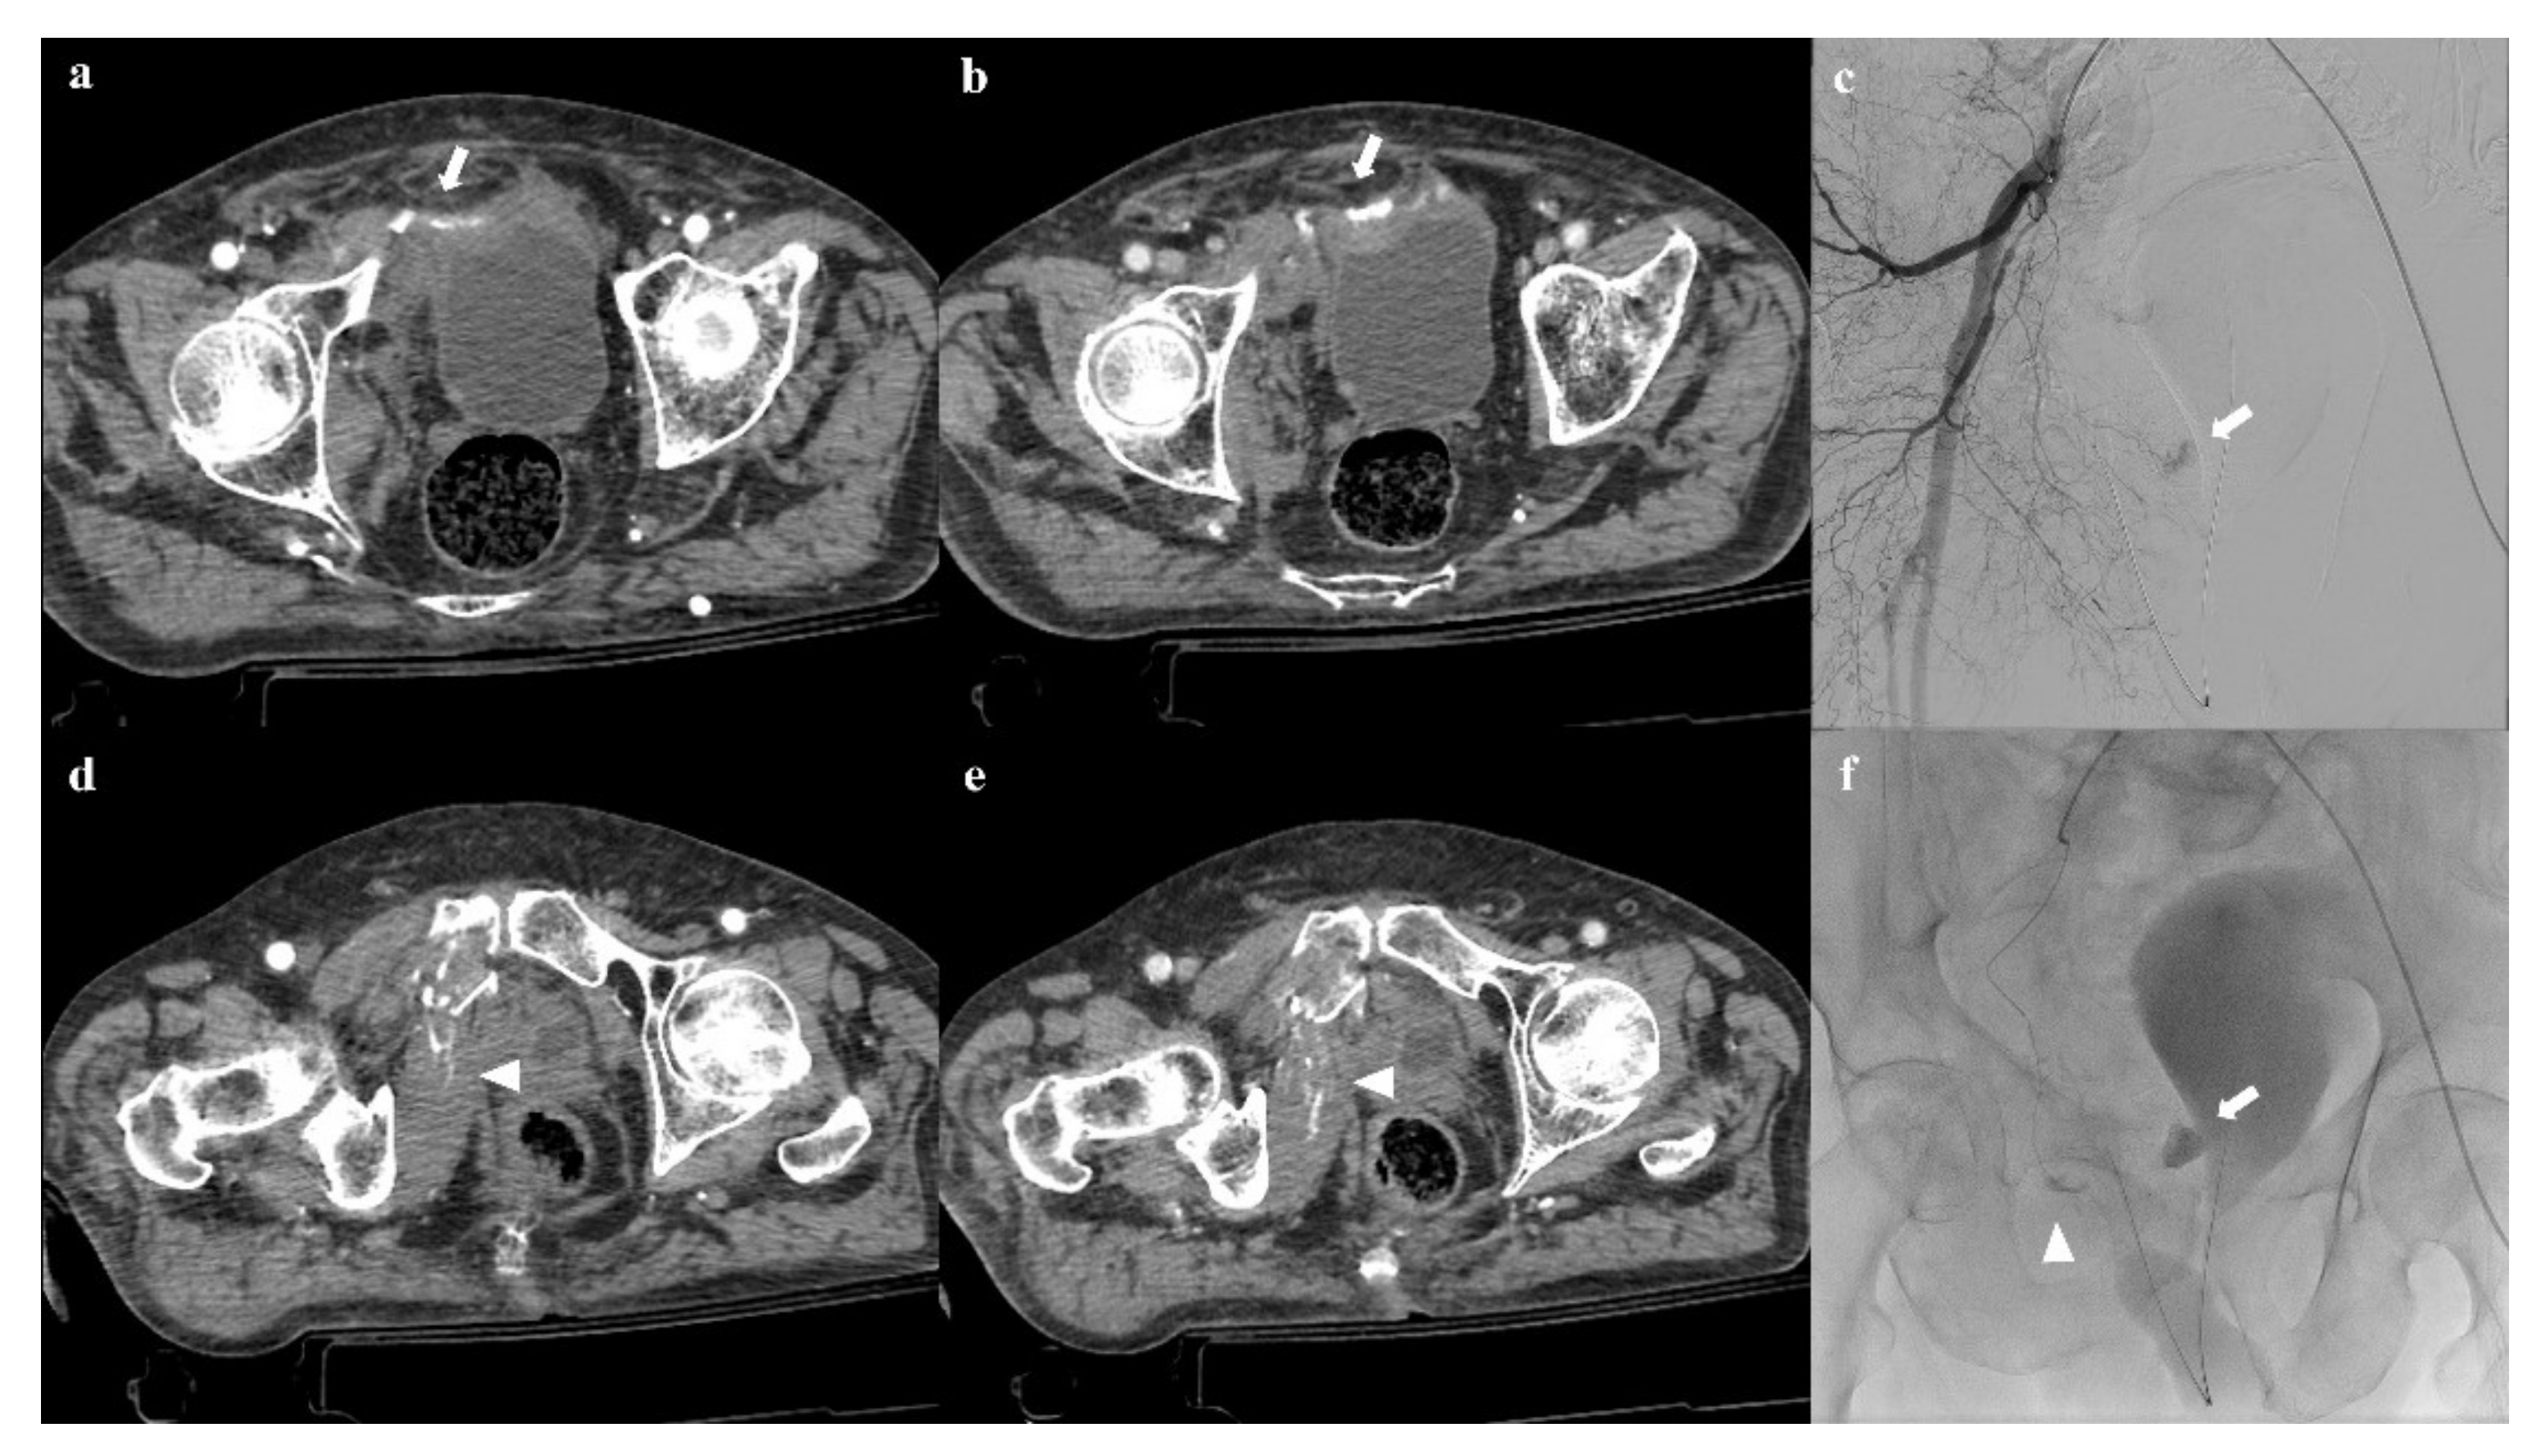

Active bleeding in the region of the pubic symphysis and pubic rami indicate an injury of the internal pudendal artery, the obturator artery, or inferior epigastric artery (Figure 10). Instead, active bleeding near the iliac wing and the sacroiliac joint indicates an injury of the superior or inferior gluteal artery, iliolumbar artery, or sacral arteries (Figure 11) [47].

Figure 10. Pelvic ring trauma, characterized by fracture of right superior and inferior pubic rami. Axial CT image in the arterial phase shows active extravasation of contrast medium near the right superior pubic branch (arrow in (a)), which increases in the venous phase of the examination (arrow in (b)). Similar active extravasation is documented near the internal obturator muscle (arrowheads in (d,e)). Selective angiography confirmed the two blood extravasation spots, with origin from branches of the right obturator artery (arrows and arrowhead in (c,f)); both the bleeding spots were optimally embolized.